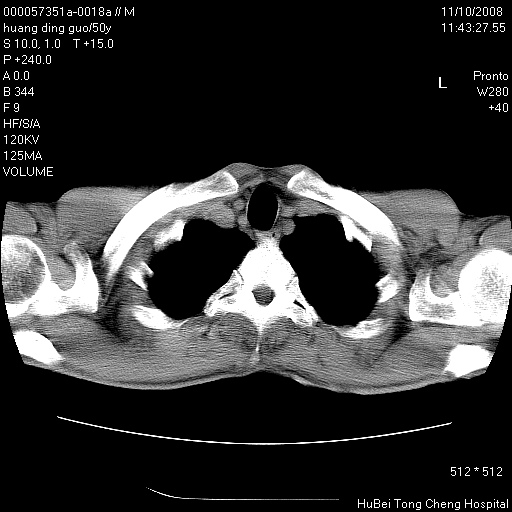

患者 男,50岁。左侧腰背部疼痛3月余,伴消瘦。平素健康,无传染病史。

胸部ct轴位平扫(层厚10mm,螺距1.5,重建间隔10mm),图像如下:

左肺下叶背段有一厚壁空洞,外壁呈锯齿状伴毛刺改变。空洞相邻胸膜有牵拉改变。左肺下叶血管支气管束不规则增粗,小叶间隔增厚。胸椎骨质破坏。考虑左肺下叶周围型肺癌伴左肺下叶癌性淋巴管炎、胸椎转移。

左肺下叶背段有一厚壁空洞,外壁呈锯齿状伴毛刺改变。空洞相邻胸膜有牵拉改变。左肺下叶血管支气管束不规则增粗,小叶间隔增厚。胸椎骨质破坏。考虑左肺下叶周围型肺癌伴阻塞性肺炎、胸椎转移。其他待排

左肺下叶背段有一厚壁空洞,内壁不规则,外壁呈锯齿状伴毛刺改变。空洞相邻胸膜有牵拉改变。周围呈絮状炎性改变,左肺下叶血管支气管束不规则增粗,小叶间隔增厚。胸椎骨质破坏。考虑左肺下叶周围型肺癌伴左肺下叶阻塞性肺炎、胸椎转移。